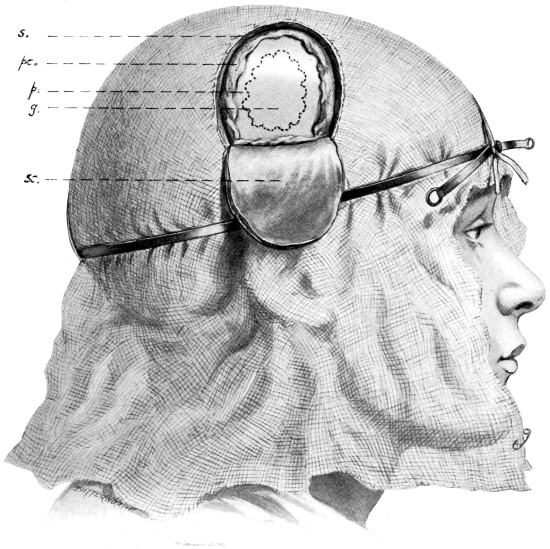

When the patient is fully under the anæsthetic, the final cleansing of the scalp is carried out and the operative field cut off from all possible sources of infection. In the States, in Cushing’s clinic, the anæsthetist is completely covered with a large sterilized sheet, which is fastened to the head of the patient. In this country we prefer that our anæsthetist should have full knowledge of the progress of the operation, and I think that the advantages are with us. In any case, the whole head is enveloped in gauze, two or three layers thick and about 18 inches square. This sheet is thrown over the patient’s head and maintained in position by means of the scalp-tourniquet (see pp. 14, 15). Around this sterilized towels are arranged, either fastened to one another or stitched to the scalp. When the operation is conducted in the temporal region the towels, unless fastened to the skin by means of a few sutures or safety-pins, tend to become displaced, and by so doing add to the risk of wound infection.

All surgeons must have appreciated the difficulty attendant on the application of forceps to, and the ligature of, divided scalp-vessels. The patient may lose a considerable quantity of blood, and much valuable time will be wasted before the more essential part of the operation is commenced. All this can, under ordinary circumstances, be avoided by the use of the scalp-tourniquet. As used by Cushing it consists of a rubber ring fashioned after the style of an Esmarch’s tourniquet, encircling the head and passing from the lower frontal region in front, above the ears, to the lower occipital region behind. A median tape, passing from glabella to occiput, prevents any tendency for the tourniquet to slip down over the eyes, at the same time acting as a convenient landmark for the superior longitudinal sinus.

The tourniquet, when applied with the correct pressure, should, under ordinary circumstances, completely control all hæmorrhage from the divided scalp-vessels. It should be noted, however, that[14] bleeding will be rather increased than otherwise if the tourniquet be so loosely applied as to impede the venous return without compressing the scalp arteries. A little experience will soon enable the operator to gauge the requisite pressure.

Fig. 4. The Scalp-tourniquet. Front View.

Fig. 5. The Scalp-tourniquet. Back View.

There is one other exception to the satisfactory working of the scalp-tourniquet. In the presence of a superficial cerebral tumour, especially when of a malignant nature, the normal communication between the intra- and extra-cranial vascular systems may be so exaggerated that those scalp-vessels which receive diploic and emissary venous communications will give rise to some trouble. This difficulty should be overcome—not by rapidity in the formation[15] and turning down of the flap—but by clipping each vessel as exposed or divided, by the application of pressure and by foraminal occlusion (see also p. 17).

I found Cushing’s tourniquet rather inconvenient in its application, and, after various modifications, am accustomed to use the one depicted in the illustration. It consists of two flat metal bands connected posteriorly by a strong rubber connecting link, the two bands passing in front through a metal fixation piece possessing a screw which, when tightened up, allows of the maintenance of the desired pressure. The median tape, previously mentioned, helps to keep the tourniquet in position.

The tourniquet is applied as follows: the whole head is enveloped in gauze—two or three layers thick, and cut to the size and shape of a large handkerchief. The tourniquet is slipped over the head,[16] as low down as possible, and then tightened up. The median tape, having a loop behind through which the tourniquet passes, is laid in the middle line and tied round the screw on the fixation piece.

The gauze should then be moistened with saline solution or some mild antiseptic, so that it clings tightly to the underlying scalp and becomes sufficiently translucent to allow of the recognition of any underlying landmarks that may have been previously mapped out with the scalpel, iodine, silver nitrate, or aniline pencil.

The scalp-flap is then framed by incisions carried down to the bone, through gauze and scalp, in one sweep. The flap is turned down and covered with gauze. By the adoption of this method hæmorrhage from scalp-vessels is efficiently controlled and the risk of wound infection is reduced to a minimum.